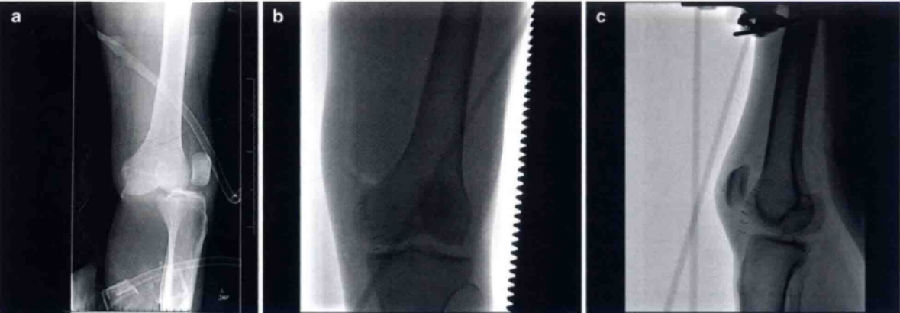

尽管该分型系统已被使用许多年,但是仍有一定的局限性。胫骨和股骨位置分型对于同时并存的损伤诊断十分有用,如血管或神经损伤。前向和后向脱位很有可能合并围动脉损伤。然而,由于所有的分型都有可能合并血管损伤,不管是哪种脱位,医帅都应高度警惕是否存在血管损伤。位置分型也可以协助确定复位方式,但是大多数脱位通过轴向牵引很容易复位。当医师在确定后外侧脱位时该分型十分有用(图3)。警惕股骨内侧髁钮扣孔样通过内侧关节囊组织,卡压陷入的内侧副韧带或内侧结构时,通常是不能够复位的。后外侧膝关节脱位特征性的标志是沿着内侧膝关节间隙的内侧皮肤的“深沟征”(medial skin furrowing),通常会显示出股骨髁远端的关节面的轮廓。对这种情况有必要迅速复位,否则股骨内侧髁的压迫会使皮肤和(或)内侧副制带坏死。发生后外侧脱位时骨科医师应高度警惕切开复位的可能性。同时。这种脱位也经常合并腓总神经损伤。

图3 a为后外侧脱位的印象学检查。这种膝关节脱位是可复性的,需要做一个将MCL插入关节的开放性复位。b和c分别是复位后的前后位片和侧位片